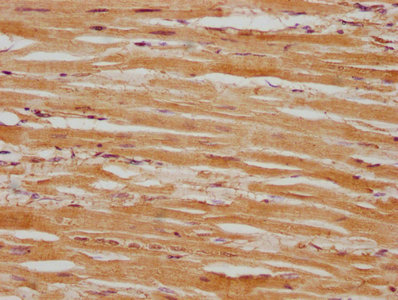

IHC image of CSB-PA618751LA01HU diluted at 1:100 and staining in paraffin-embedded human heart tissue performed on a Leica BondTM system. After dewaxing and hydration, antigen retrieval was mediated by high pressure in a citrate buffer (pH 6.0). Section was blocked with 10% normal goat serum 30min at RT. Then primary antibody (1% BSA) was incubated at 4°C overnight. The primary is detected by a biotinylated secondary antibody and visualized using an HRP conjugated SP system.